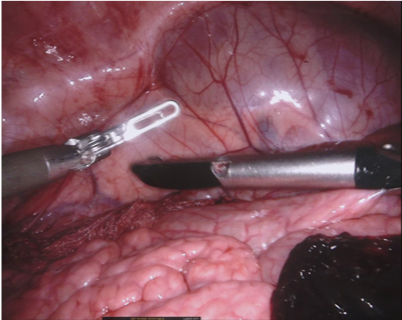

As robotic minimally invasive surgery has developed, with platforms such as da Vinci becoming the de-facto standard-of-care for certain urological, gynecological and general surgical procedures, there has been an increase in focus in how assistive systems based on computer vision and machine learning can improve surgeon performance and patient outcomes. Many potential applications are dependent on scene understanding and for this, accurate segmentation of instruments is an important component. For instance, instrument tracking algorithms which underlie automation and guidance assistance often build upon segmentation [4] or alternatively masking augmented reality overlays of 3D imaging modalities requires pixel labelling of the instruments to prevent their occlusion (see Fig. 1).

Our challenge was made up of 3 sub-problems. The first was binary instrument segmentation, where each frame was separated into da Vinci Xi instruments and a background class, which contained an ultrasound probe, surgical clips and porcine tissues. The second task was instrument part segmentation, where we scored the participants on whether they could correctly segment each articulating part of the instrument (see Fig. 3). Our final task was to segment and classify the instruments (see Fig. 4).

Our dataset was made up of 10 sequences of abdominal porcine procedures recorded using da Vinci Xi systems. From each procedure we selected active sequences where significant instrument motion and visibility was observed and sampled 300 frames at a rate of 1 Hz. In cases where instrument motion ceased for several frames we manually removed these frames and extended the sequence so that exactly 300 frames remained. We provided left and right eye images from the stereo camera on the Xi system and also provided camera calibration information in case participants wished to use stereo reconstruction as a feature.

We provided the first 225 frames of 8 sequences as training data and kept the last 75 frames of those 8 sequences as test data. 2 of the full 300 frame sequences were kept as test sequences. Test labels were kept hidden from the participants. Our datasets contain 7 different robotic surgical instruments. The Large Needle Driver, Prograsp Forceps, Monopolar Curved Scissors, Cadiere Forceps, Bipolar Forceps, Vessel Sealer and additionally a drop-in ultrasound probe, which is typically held in the jaws of the Prograsp Forceps instrument. Samples from the training datasets are depicted in Fig. 2 and examples of the different instrument types are shown in Figure 3 and 4.